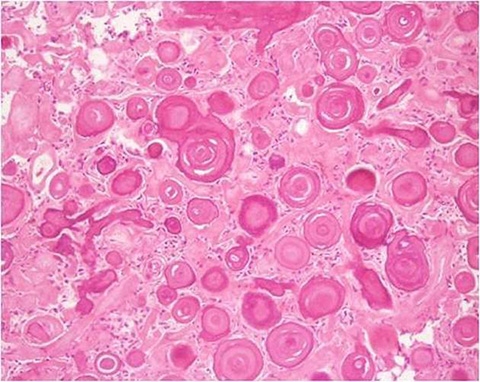

When you look at those biopsies, the pathologist makes the decision as to whether or not it's in one of these six categories just based on the look of it. You would think that's a pretty precise activity, right? For example, there are classic findings for papillary cancer like Orphan Annie nuclei, intranuclear grooving, some psammoma bodies, all these things. And they all sound very definitive, pretty straightforward like it's a binary thing: you have it or you don't. But in reality, when you further parse out each of those findings, like in large nuclei, the real question is how large? How much bigger does it have to be? Two times, three times, two and a half times, 2.7 times?

When humans are looking at these slides, basically, we're doing Gestalt Theory. You're looking at it and you're saying, "Oh, that looks like thyroid cancer. I can't tell you exactly why, but I know that these nuclei are bigger than they should be. I don't know exactly how much bigger." A lot of it is just that gut feeling that the pathologist ends up having, but there are probably some very clear quantitative guidelines that you can actually use to apply.

Humans can't do all of those calculations on any given slide, we just physically can't. But computers can do it in a very easy, straightforward way. So, Jen and I have this belief that by using advanced neural networks and training them with thousands and thousands of biopsy samples, ultrasound data, and correlating it with the final pathology results from a surgical specimen, we can actually program the neural network to give us a better estimate of the cancer risk.